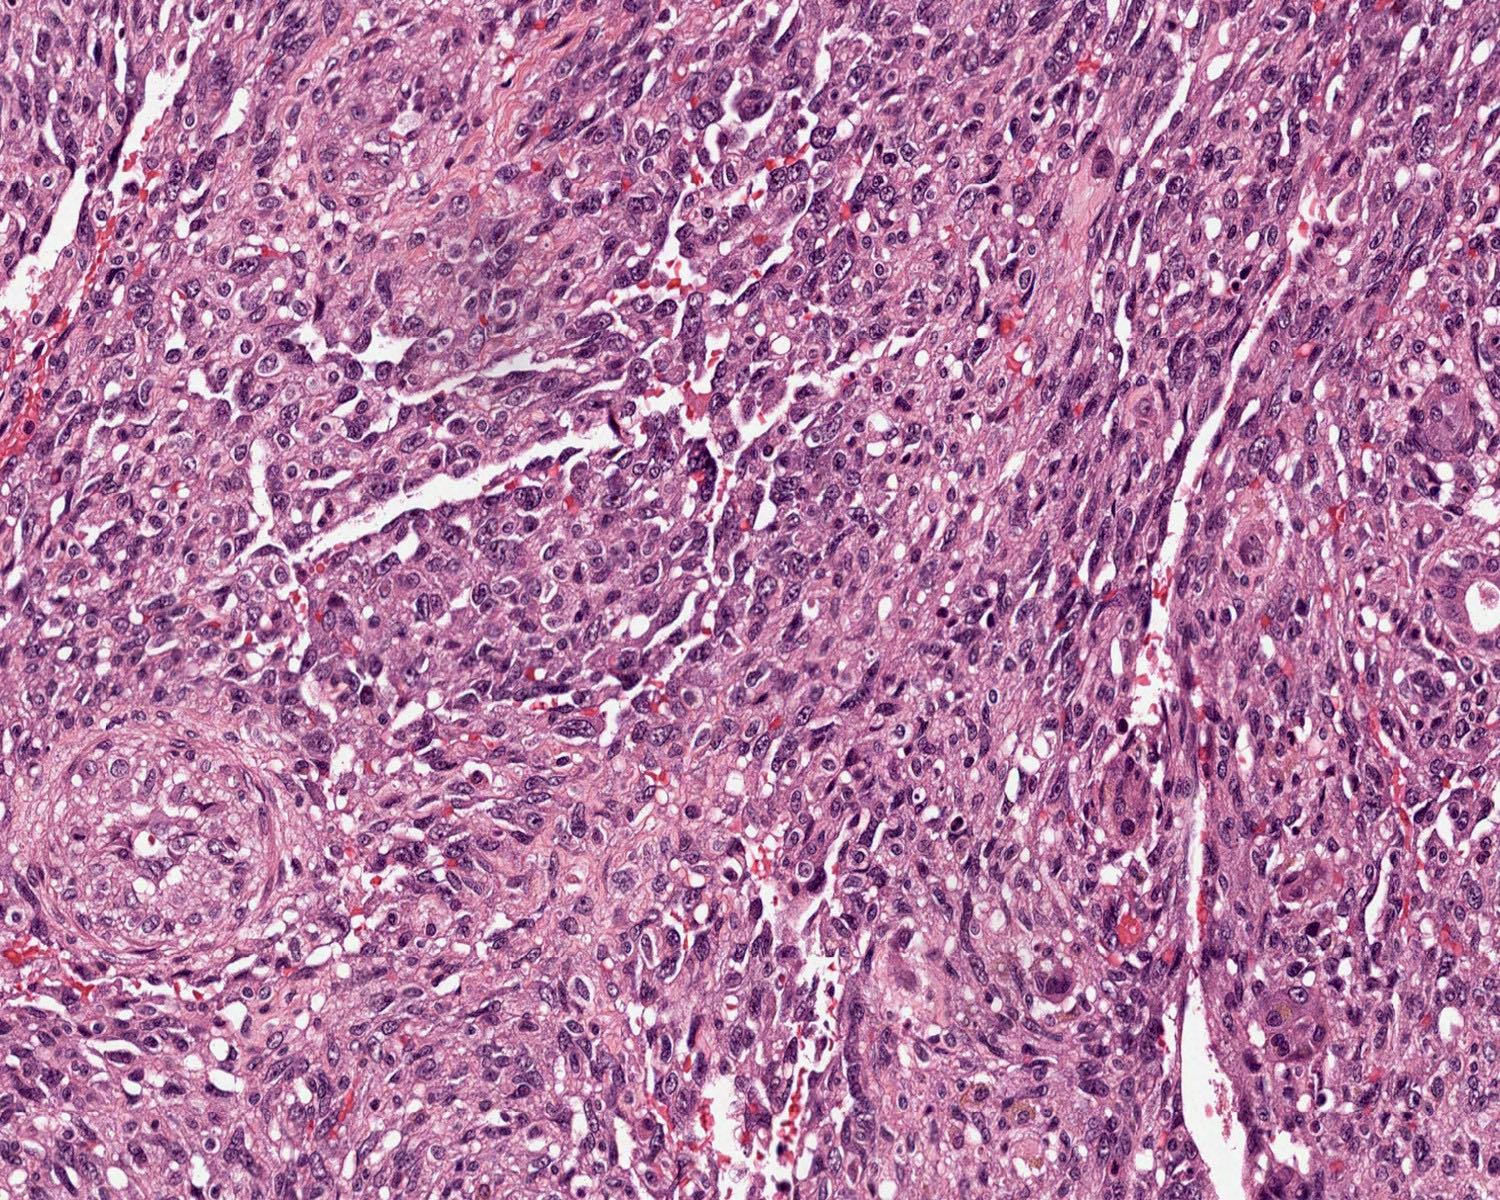

Microscopic (histologic) description

- 2 main histologic growth patterns were described (Am J Surg Pathol 2019;43:581)

- Non-mass forming

- Sinusoidal

- Dilated sinusoids lined by atypical endothelial cells seen in angiosarcoma with hyperchromatic nuclei

- Peliotic

- Blood pools and fibrin surrounded by hepatocytes

- Peripheral clusters of atypical endothelial cells seen in angiosarcoma mixed with inflammatory cells may extend into the sinusoids

- Mass forming

- Vasoformative shows architectural complexity and interconnecting vascular channels

- Anastomosing vessels and haphazard vascular channels

- Endothelial cells show tufting, atypia and mitotic figures

- Nonvasoformative shows epithelioid to spindled morphology

- Epithelioid morphology (epithelioid angiosarcoma) is most common (Am J Surg Pathol 2004;28:298)

- Solid nests or sheets of tumor cells

- Tumor often invades into sinusoids and hepatic venules at the periphery

- Cells have eosinophilic cytoplasm and oval nuclei

- Chromatin can be vesicular

- Multinucleated giant cells can be present

- Unusual growth patterns (Am J Surg Pathol 2019;43:581)

- Whorls of spindle cells in a background of chronic inflammation and loose myxoid to sclerotic stroma

- Infantile hemangioma-like angiosarcoma

- Hemangioma-like angiosarcoma

Microscopic (histologic) images

A 55 year old man presents with abdominal pain, weight loss and hepatomegaly. Laboratory studies reveal elevated liver enzymes but normal alpha fetoprotein levels. A liver core needle biopsy is performed. ERG immunohistochemistry is shown in the second image above. What is the most likely diagnosis?

E. Liver angiosarcoma. The histopathology shows nests and sheets of highly atypical neoplastic cells with hyperchromatic and pleomorphic nuclei, which are highlighted by ERG immunohistochemistry in the second image above. This makes liver angiosarcoma the most likely diagnosis.